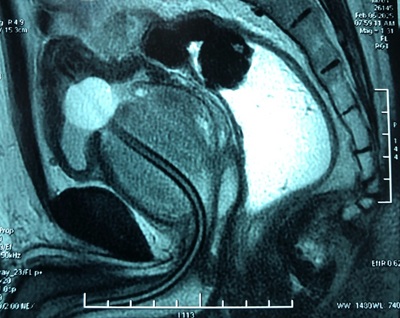

Hình: Kết quả chụp MRI của bệnh nhân với tuyến tiền liệt rất to

Mới đây, Bệnh viện Trường Đại học Y Dược Cần Thơ đã phẫu thuật thành công một ca bóc nhân tuyến tiền liệt bằng laser HoLEP với kích thước tuyến lên đến 200gr. Đây là trường hợp bệnh nhân có tuyến tiền liệt to nhất mà chúng tôi từng phẫu thuật. Nhờ sự phối hợp chuyên môn cao của đội ngũ y bác sĩ cùng trang thiết bị hiện đại, bệnh nhân đã hồi phục nhanh chóng, đi tiểu dễ dàng và xuất viện chỉ sau 48 giờ. Đây là một bước tiến quan trọng, khẳng định năng lực và sự phát triển không ngừng của bệnh viện trong lĩnh vực tiết niệu.